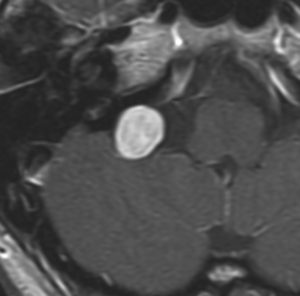

症例:頸静脈孔に限局するもの

小さな頸静脈孔内に限局する神経鞘腫です。無症状で発見されたものであれば,そもそも治療の必要性がありません。多少大きくなっても症状はでません。また手術は侵襲が大きいので,必要があれば定位放射線治療で治療します。定位放射線治療しても何の有害事象(副作用)も出ないものです。